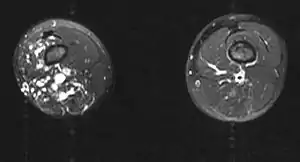

| MRI | |